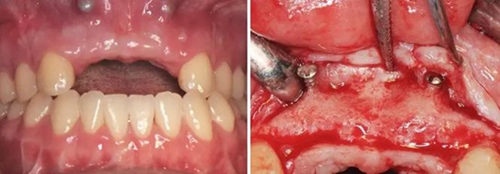

(3)2015年2月:Onlay植骨后6月行種植手術(shù)

術(shù)前再次拍攝CBCT,顯示牙槽嵴寬度較植骨當(dāng)日有一定量的吸收,測(cè)量可用骨寬度,12位點(diǎn)為3.7mm-10.9mm,22位點(diǎn)為5mm-10.9mm。做術(shù)前準(zhǔn)備,用0.12%的復(fù)方氯己定漱口液含漱3次,每次15ml,含漱1min。采用無(wú)痛麻醉機(jī)(STA),復(fù)方鹽酸阿替卡因進(jìn)行口內(nèi)局部浸潤(rùn)麻醉,將麻醉藥物緩慢注入術(shù)區(qū)的牙槽嵴骨膜下方。翻瓣并剝離粘骨膜后充分暴露牙槽骨,取出先前固定骨塊的鈦釘,確認(rèn)植入位點(diǎn),小球鉆定點(diǎn),使用BEGO骨水平種植體及其配套器械(BEGO公司,德國(guó)),根據(jù)擬植入種植體長(zhǎng)度以及直徑大小,逐級(jí)備洞,植入2顆種植體,均為BEGO,RSX植體,直徑為3.75mm,長(zhǎng)度為15mm,獲得35Ncm以上植入扭矩,用種植體穩(wěn)定性測(cè)量?jī)xOsstell ISQ (Osstell公司,瑞典)測(cè)量ISQ值:12、22位點(diǎn)種植體均為79,種植體平臺(tái)位于骨下約1mm,術(shù)后上愈合基臺(tái),嚴(yán)密縫合創(chuàng)口。

圖11 植骨后6月種植術(shù)前 圖12 種植術(shù)前翻瓣后見少量鈦釘螺紋暴露

圖13 取出鈦釘后 圖14 攜帶體示植體位置方向良好

圖15 種植術(shù)后 圖16 種植后嚴(yán)密縫合創(chuàng)口

圖17 CBCT測(cè)量骨量變化 圖18 早期修復(fù)戴牙當(dāng)天